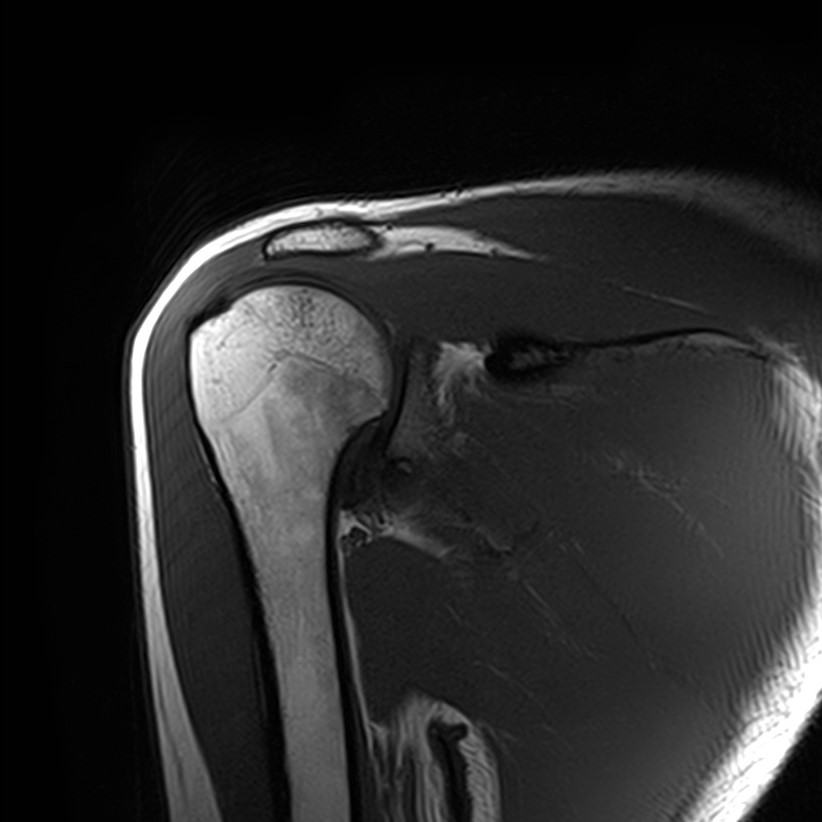

Магнитно-резонансная томография позволяет выявлять следующие заболевания плечевого сустава:

• Дегенеративно-дистрофические заболевания, в частности деформирующий остеоартроз, при котором происходит истончение хряща на фоне нарушения его питания. В результате развивается дисфункция сустава и деформация костных структур.

• Воспалительные заболевания с поражением как самого сустава (артрит), так и окружающих мягких тканей (синовит, бурсит, тендовагинит).

• Развитие в области плечевого сустава как доброкачественных, так и злокачественных новообразований. Поражение сустава может быть первичной опухолью, исходящей из костной ткани или мягких тканей, либо за счет метастазирования из отдаленных очагов.

• Травмы плечевого сустава, различные переломы, при этом наиболее часто встречаются вывихи, что обусловлено анатомией сустава. Нередко травмы сустава с разрывом связок и сухожилий ведут в дальнейшем к развитию нестабильности плечевого сустава и могут стать причиной формирования привычных вывихов.